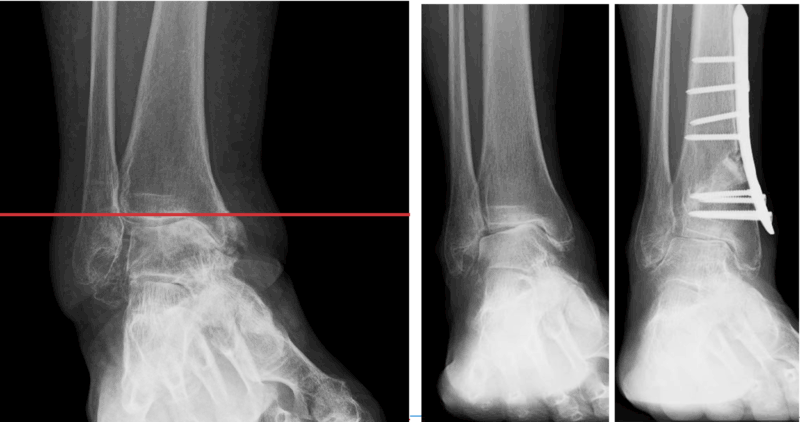

矯正骨切り術

関節症変化の進行に伴う軟骨のすり減りが内側部分にとどまり、比較的若年の活動性が高い方が対象となります。

レイクタウン整形外科病院の当センターでは、関節上部の骨の内側を斜めに切って外向きに開く矯正をかけ、開大部には骨盤から採取した骨をはめ込んで金属プレートする方法(脛骨遠位斜め骨切り術:DTOO)を採用しており、この処置によって軟骨がすり減へった内側部に集中している負担を比較的に健常な外側部逃がしてやるとともに、横方向の関節安定性を改善させて、炎症に伴う痛みや腫れが起こりにくい関節構造の回復を目指します。

骨切り部の確実な癒合得るための荷重制限(松葉杖保護)や関節運動の回復訓練など術後リハビリが重要となり、術後回復にも時間がかかる手術法ですが、一旦骨癒合が完成すれば活動性の制限は少ないため、重労働を伴う職種やスポーツ活動の希望者にも適しています。